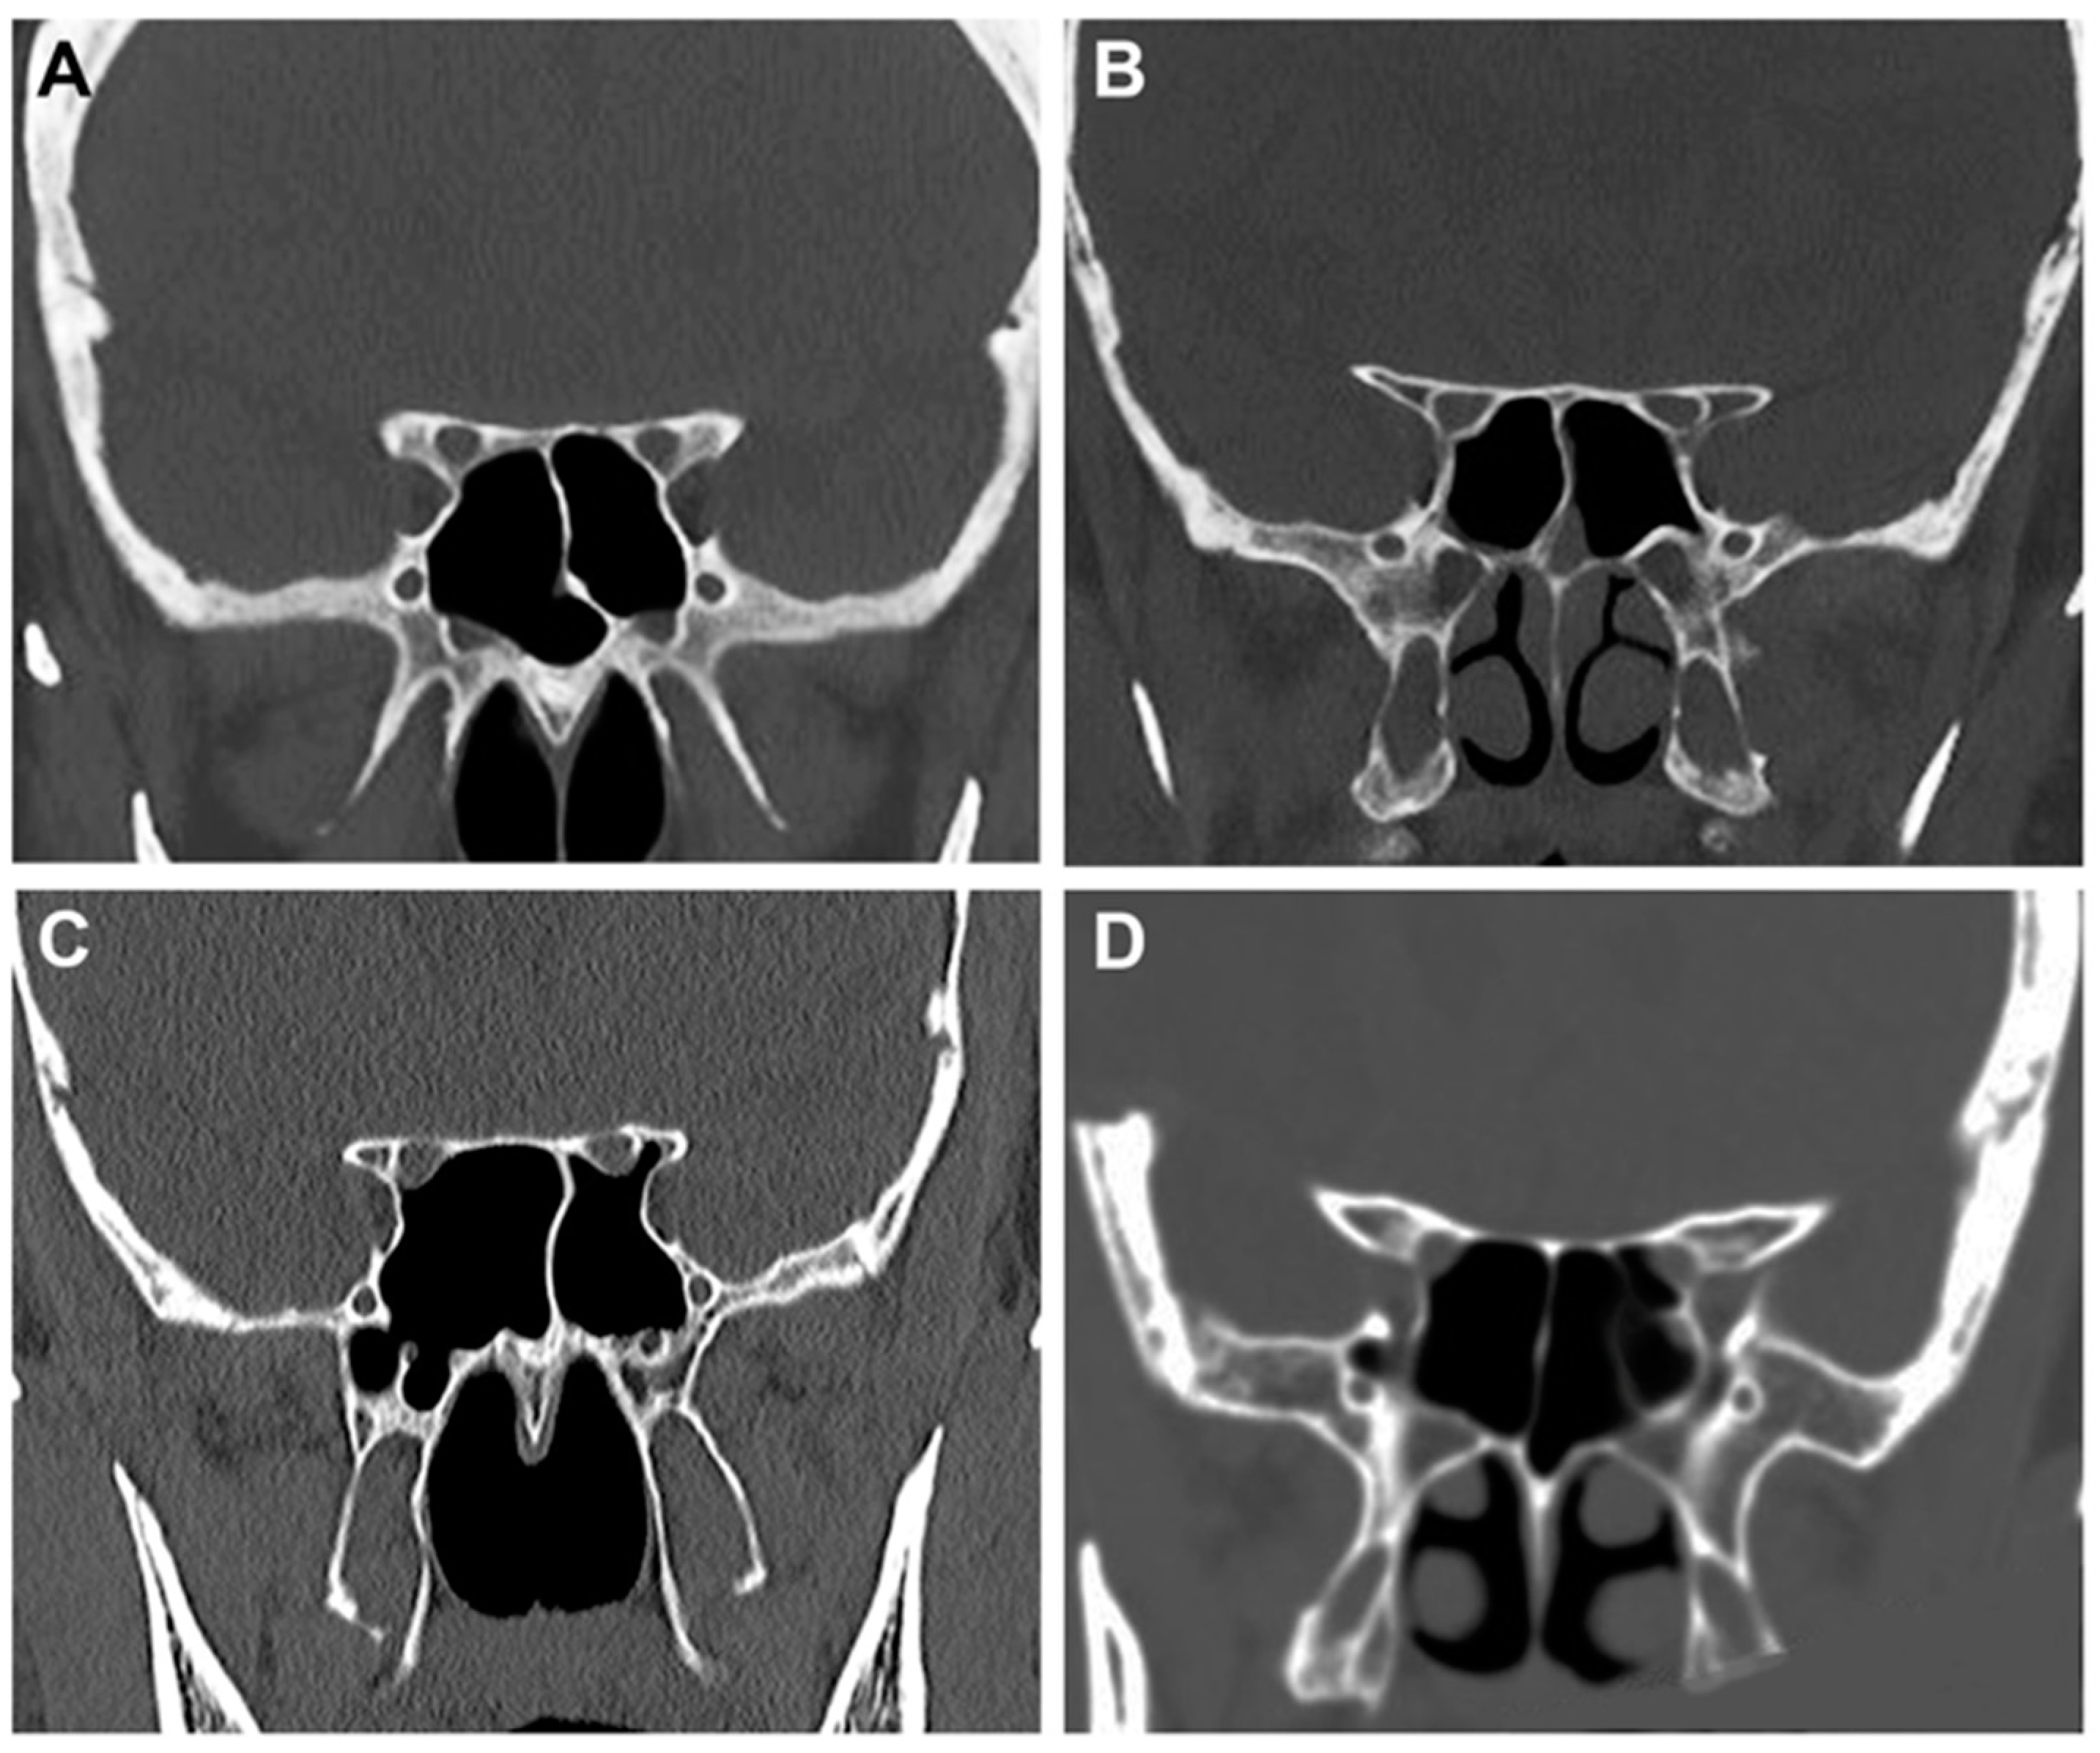

2.2. Radiological Study

- Type 1: the optic canal was adjacent to the sphenoid sinus (SpS) without impression;

- Type 2: the optic canal caused an impression on the SpS;

- Type 3: the optic canal was identified in the SpS;

- Type 4: the optic canal was found lateral to the SpS and the posterior ethmoid sinus (presence of Onodi cell or spheno-ethmoidal air cell).

| DeLano’s classification | |

| Type 1 | 74.5% (149 patients) |

| Type 2 | 17% (34 patients) |

| Type 3 | 7% (14 patients) |

| Type 4 | 1.5% (3 patients) |